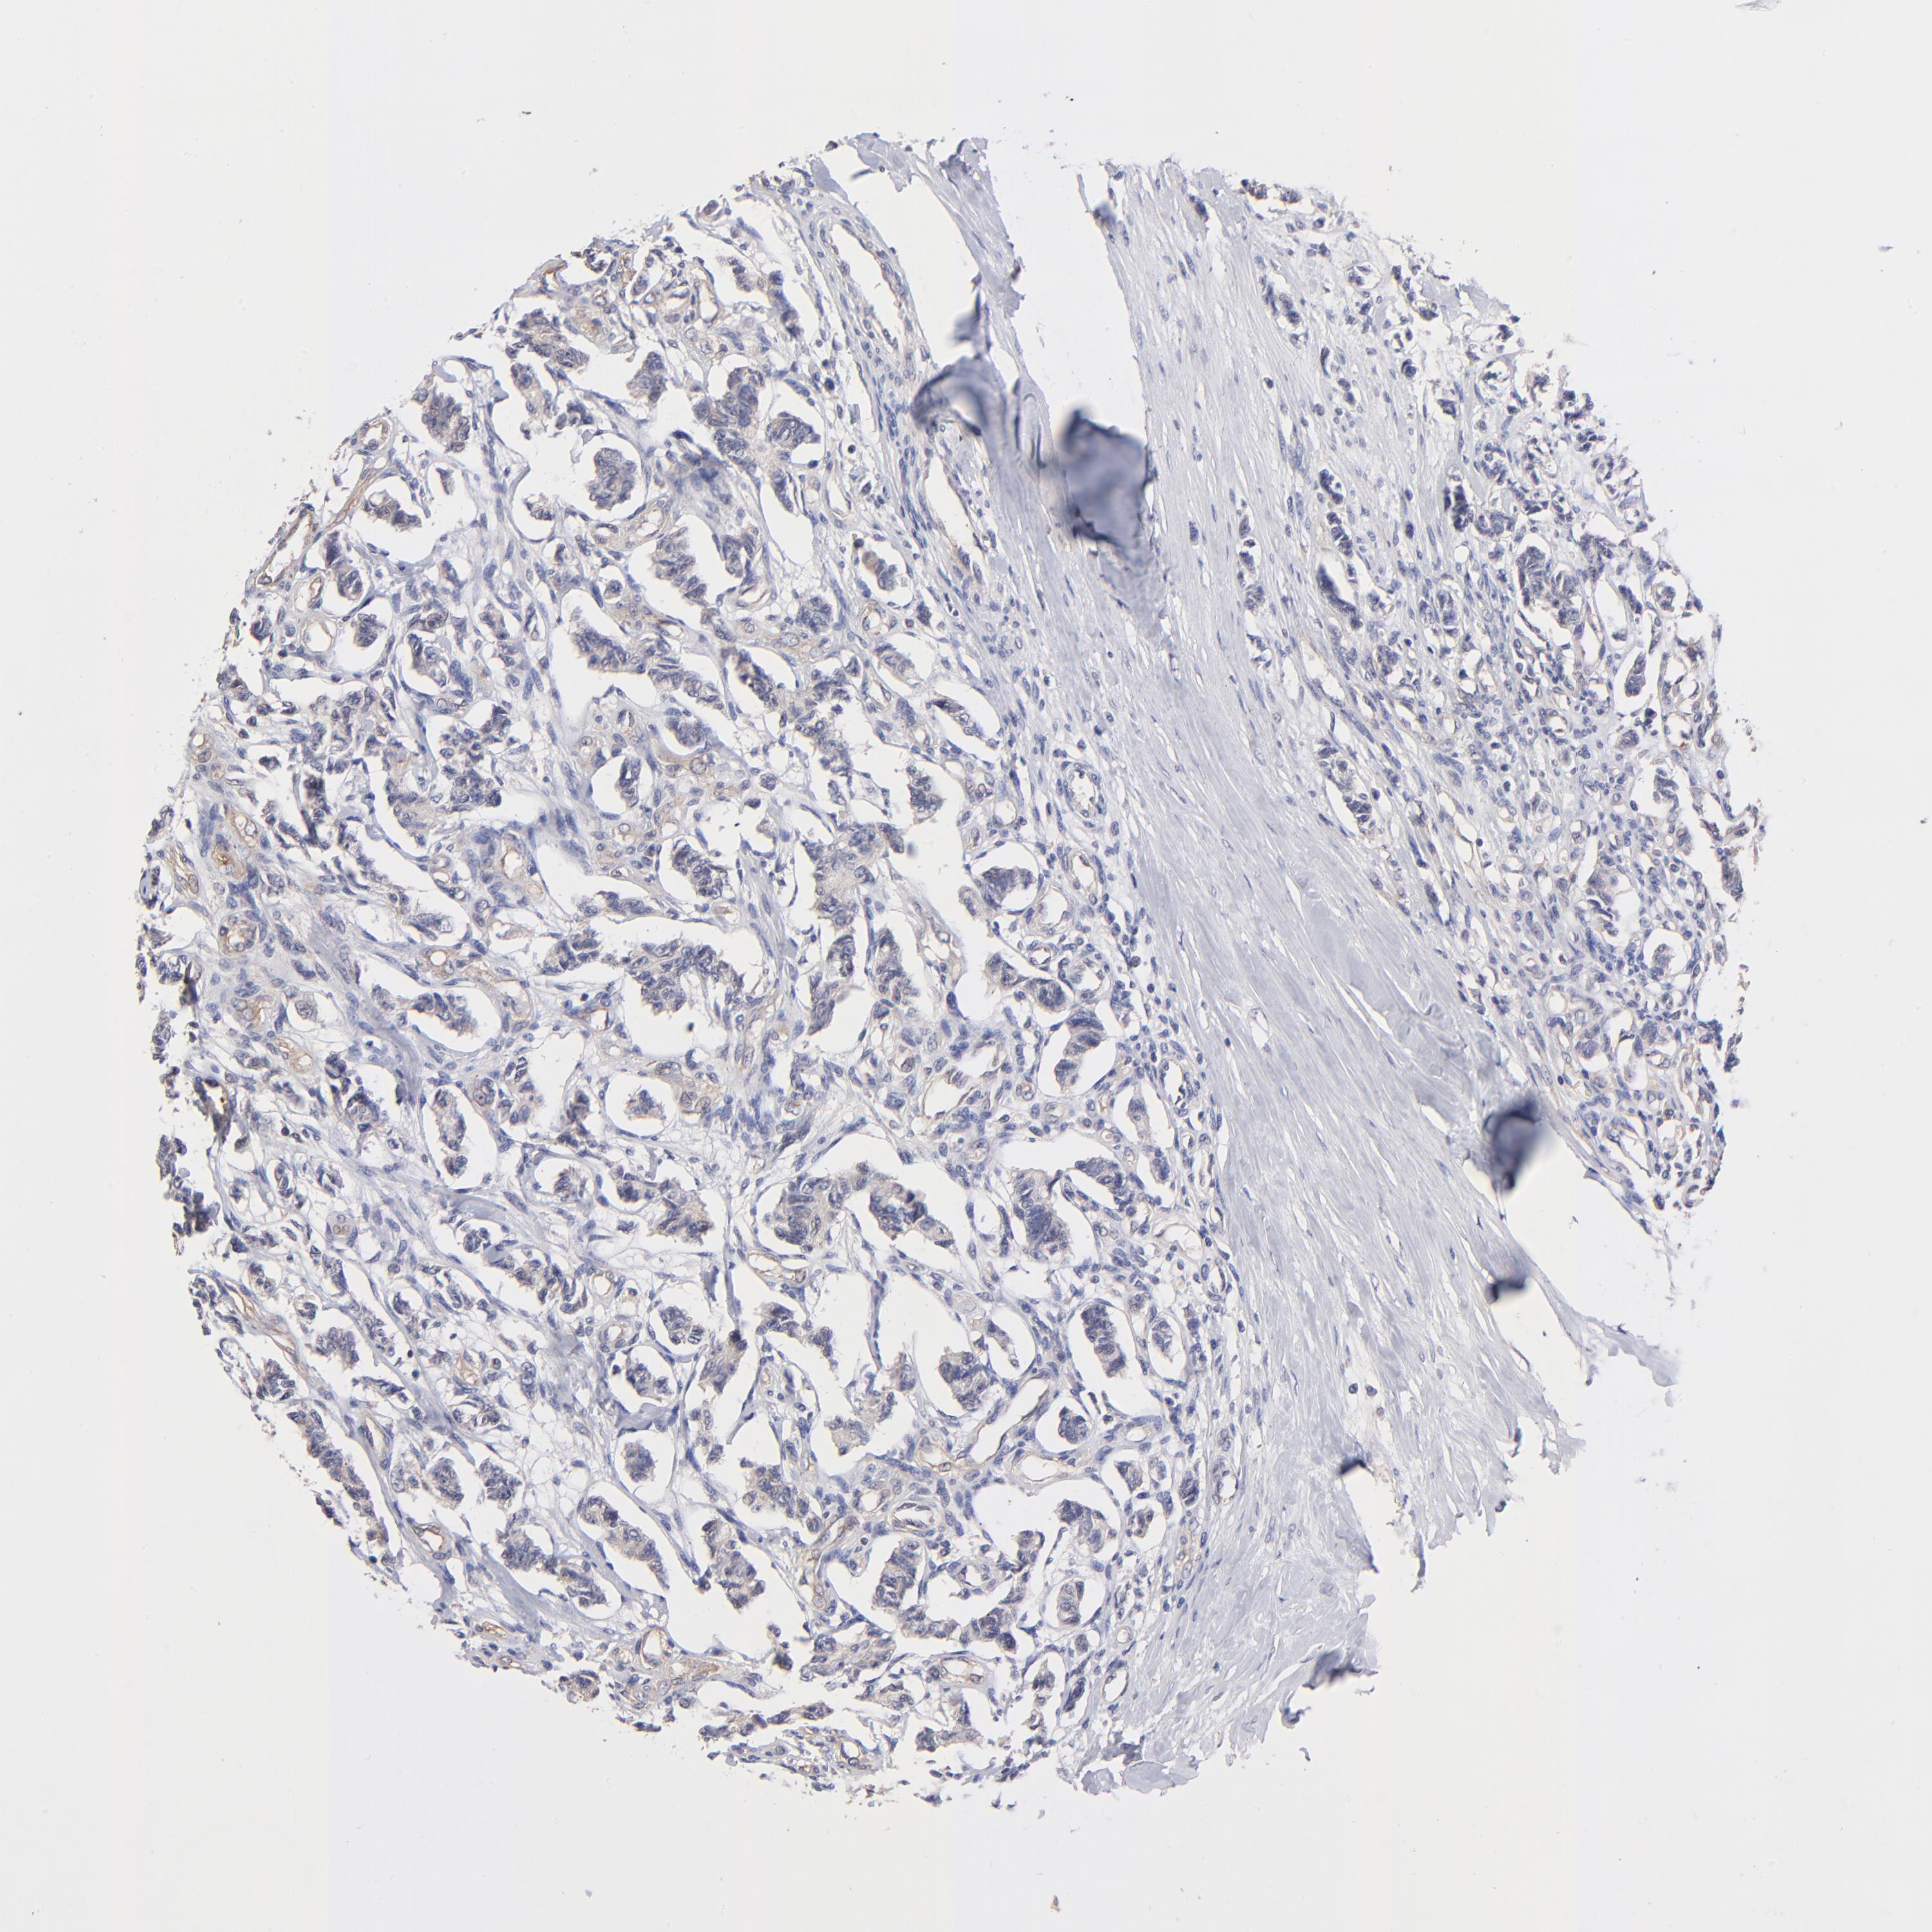

KIDNEY RENAL CLEAR CELL CARCINOMA (VALIDATION) - Interactive survival scatter ploti

The Survival Scatter plot shows the clinical status (i.e. dead or alive) for all individuals in the patient cohort, based on the same data that underlies the corresponding Kaplan-Meier plots. Patients that are alive at last time for follow-up are shown in blue and patients who have died during the study are shown in red.

The x-axis shows the expression levels (FPKM) of the investigated gene in the tumor tissue at the time of diagnosis. The y-axis shows the follow-up time after diagnosis (years). Both axes are complimented with kernel density curves demonstrating the data density over the axes. The top density plot shows the expression levels (FPKM) distribution among dead (red) and alive patients (blue). The right density plot shows the data density of the survived years of dead patients with high and low expression levels respectively, stratified using the cutoff indicated by the vertical dashed line through the Survival Scatter plot. This cutoff is automatically defined based on the FPKM cutoff that minimizes the p-score. The cutoff can be changed by dragging the vertical line or by entering a cutoff value in the square labeled "Current cut-off".

Under the Survival Scatter plot the p-score landscape (black curve; left axis) is shown together with dead median separation (red curve; right axis). Dead median separation is the difference in median mRNA expression between patients who have died with high and low expression, respectively. It is calculated as follows: median FPKM expression of dead patients with high expression - median FPKM expression of dead patients with low expression. This is intended to aid the user in visually exploring custom cutoffs and the associated p-scores and dead median separation.

Individual patient data is displayed and can be filtered by clicking on one or more of the category buttons on the top of the page. Categories describing expression level and patient information include: high, low, alive, dead, female, male and tumor stages. The scale of the x-axis can be toggled between linear and log-scale by clicking on the "x log" button. Mouse-over function shows TCGA ID, patient information and mRNA expression (FPKM) for each patient.

& Survival analysisi

Kaplan-Meier plots summarize results from analysis of correlation between mRNA expression level and patient survival. Patients were divided based on level of expression into one of the two groups "low" (under cut off) or "high" (over cut off). X-axis shows time for survival (years) and y-axis shows the probability of survival, where 1.0 corresponds to 100 percent.

ASB7 is validated prognostic, high expression is favorable in Kidney Renal Clear Cell Carcinoma (validation)

Best expression cut offi

Based on the FPKM value of each gene, patients were classified into two groups and association between prognosis (survival) and gene expression (FPKM) was examined. The best expression cut-off refers the FPKM value that yields maximal difference with regard to survival between the two groups at the lowest log-rank P-value. Best expression cut-off was selected based on survival analysis .

When clicking on this number, the vertical dashed line indicating cut-off, the interactive survival plot, and the Kaplan-Meier curve will be adjusted to show results based on the best expression cut-off.

: 7.47

TCGA RNA samplesi

RNA-seq data is reported as average FPKM (number Fragments Per Kilobase of exon per Million reads), generated by the The Cancer Genome Atlas (TCGA) .

Normal distribution across the dataset is visualized with box plots, shown as median and 25th and 75th percentiles. Points are displayed as outliers if they are above or below 1.5 times the interquartile range. FPKM values of the individual samples are presented next to the box plot.

Average pTPM 7.6

Number of samples 100